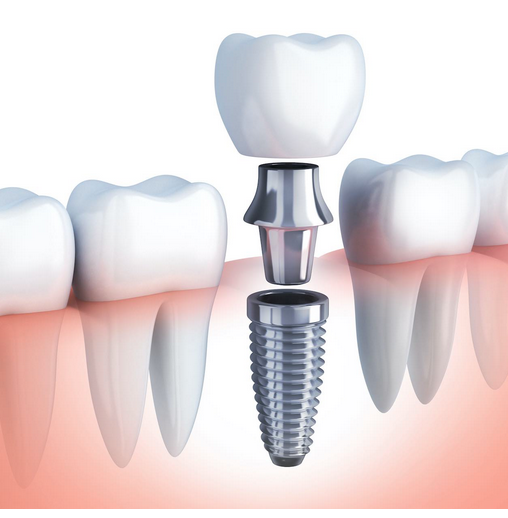

Una prótesis dental es un dispositivo diseñado para reemplazar dientes perdidos o dañados, restaurando tanto la función masticatoria como la estética del paciente. Las prótesis pueden ser fijas o removibles. Están diseñadas para adaptarse a las necesidades específicas de cada paciente